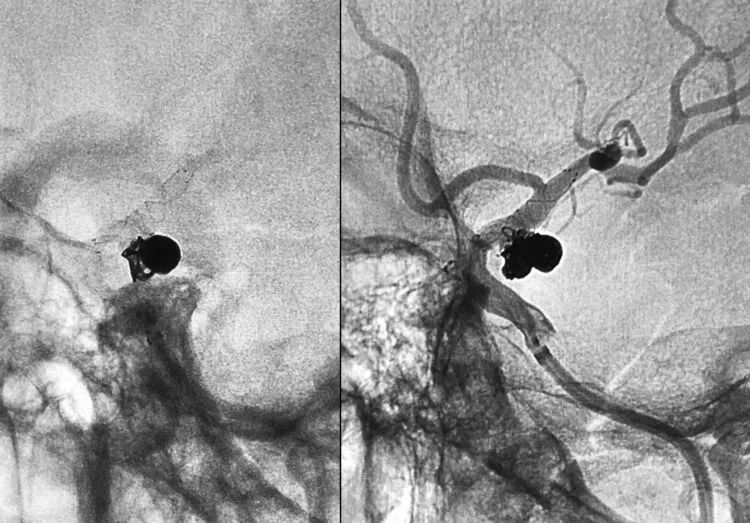

术后左颈内动脉工作位造影显示动脉瘤完全栓塞,后交通动脉壶腹保留:

双微导管栓塞流程跟上两例如出一辙,不同之处在于本例加用了支架辅助。